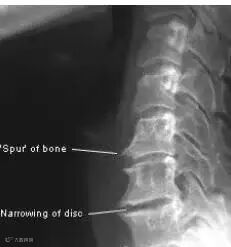

颈腰椎骨质增生系在颈腰椎退变疾病(Cervical and lumbar degenerative diseases),如椎间盘突出、椎管狭窄、椎体失稳等后出现的。脊柱的“骨刺”可能会影响到神经,这种刺激或压迫可能导致肢体的疼痛、麻木。